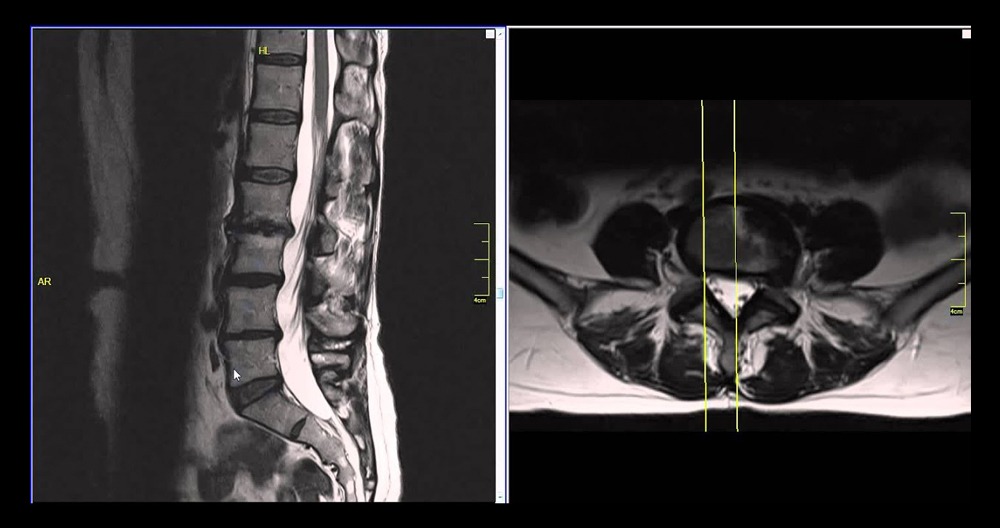

MRI Lumbar Herniated Disc

MRI is the best imaging procedure available to diagnose a herniated disk. A MRI scan can pinpoint the location of the herniated disc and allow for the measurement of herniation.

An MRI scan can help to improve the accuracy of surgery and speed up the recovery process.

Proton resonance technology is used to create soft tissue cross-sectional images of the spine using magnetic resonance imaging. These images allow the diagnostician more precise and detailed assessments of the intervertebral disk and its relationship to the neural structures. They are more accurate than traditional methods such as computed tomography (CT), and lumbar myelograms.

A systematic review of the available literature involving spinal MRI found MRI to be a highly sensitive and but less specific imaging modality for lumbar spinal conditions.For example, high sensitivity ranging between 89-100% for disc herniation have been described in previous studies.The lower specificity, 43-97% for disc herniation has been highlighted in previous literature and relates to the prevalence of asymptomatic disc degeneration and protrusions resulting in a large number of false positives.6 In a group of 57 patients with unilateral lower limb radiculopathy, only 30% of these patients had MRI findings of disc herniation and nerve root compression at the same level as the clinical prediction.Therefore, when reviewing the imaging, one must exert a degree of care when attributing the patient’s symptoms to the appearance of their lumbar spine.

An MRI scan can confirm a herniated disk diagnosis. It pinpoints the exact spot on the spine where there is herniation. It is possible to manage treatment (which may include surgery in certain cases) better and optimize patient recovery.